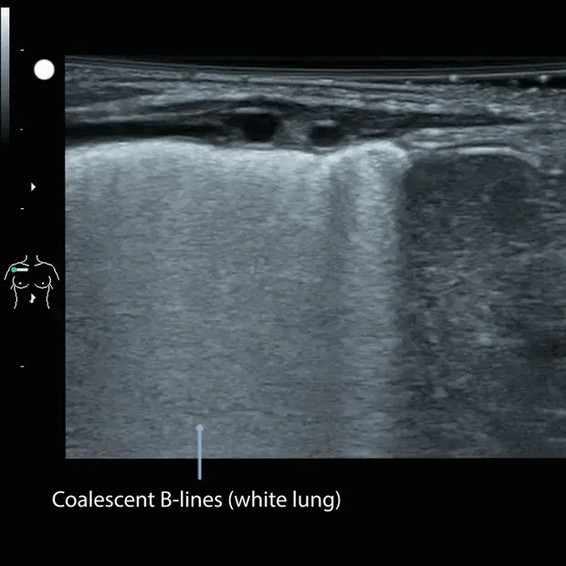

📚 Case Study: Pediatric Lung

2-week old infant male presents with respiratory distress.

What are the relevant sonographic findings in this clip?